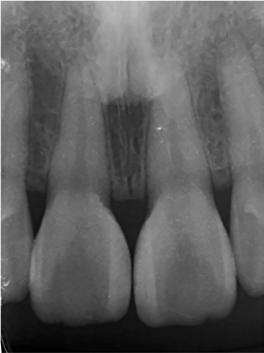

ezen a területen, a fogászat profitál az ilyen fejlesztésekből, és ma már számos kezelési megoldást kínálunk pácienseinknek. Rezidens korom alatt klinikai szakfelügyelőként dolgoztam akadémiai környezetben, ahol elsősorban kivehető fogpótlásra szoruló geriátriai betegeket kezeltem, valamint olyanokat, akiknek fix fogpótlásra, például fog- vagy implantátummal ellátott hagyományos rögzített fogpótlásra (azaz korona és híd) volt szükségük, elsősorban arany vagy fémkerámia felhasználásával. Az ezekben az években megfigyelt klinikai kudarcok és a beavatkozások invazív jellege, nevezetesen a foghúzásra vonatkozó több fúrás és egyszerűbb döntések jelentős szerepet játszottak a kutatási irányvonalam kialakításában az évek során. Ez volt az az időszak is, amikor elkezdtem többet foglalkozni az adhezív fogászattal, ami megváltoztatta a protetikai fogászat klasszikus arculatát, és határozottan kevésbé invazívvá tette azt (1. a-d ábrák). Ma, az intenzív transzlációs és klinikai kutatás eredményeként, különös tekintettel a fogászati bioanyagok alkalmazására, klinikai szakértelmem a minimálisan invazív, adhezív eljárások alkalmazására összpontosít a protetikai fogászatban, a szövődmények kezelésére és a költséghatékony kezelési lehetőségek felkínálására.

1a 1c 1b 1d

1. a-d ábrák: a) Fogerózió a molárisok okkluzális felszínén, b) maratás foszforsavval, c) minimálisan invazív műgyanta-kompozit fedőréteg levegővel történő felszívása, d) adhezív ragasztott fedőréteg a hiányzó zománc és dentin helyreállítására.